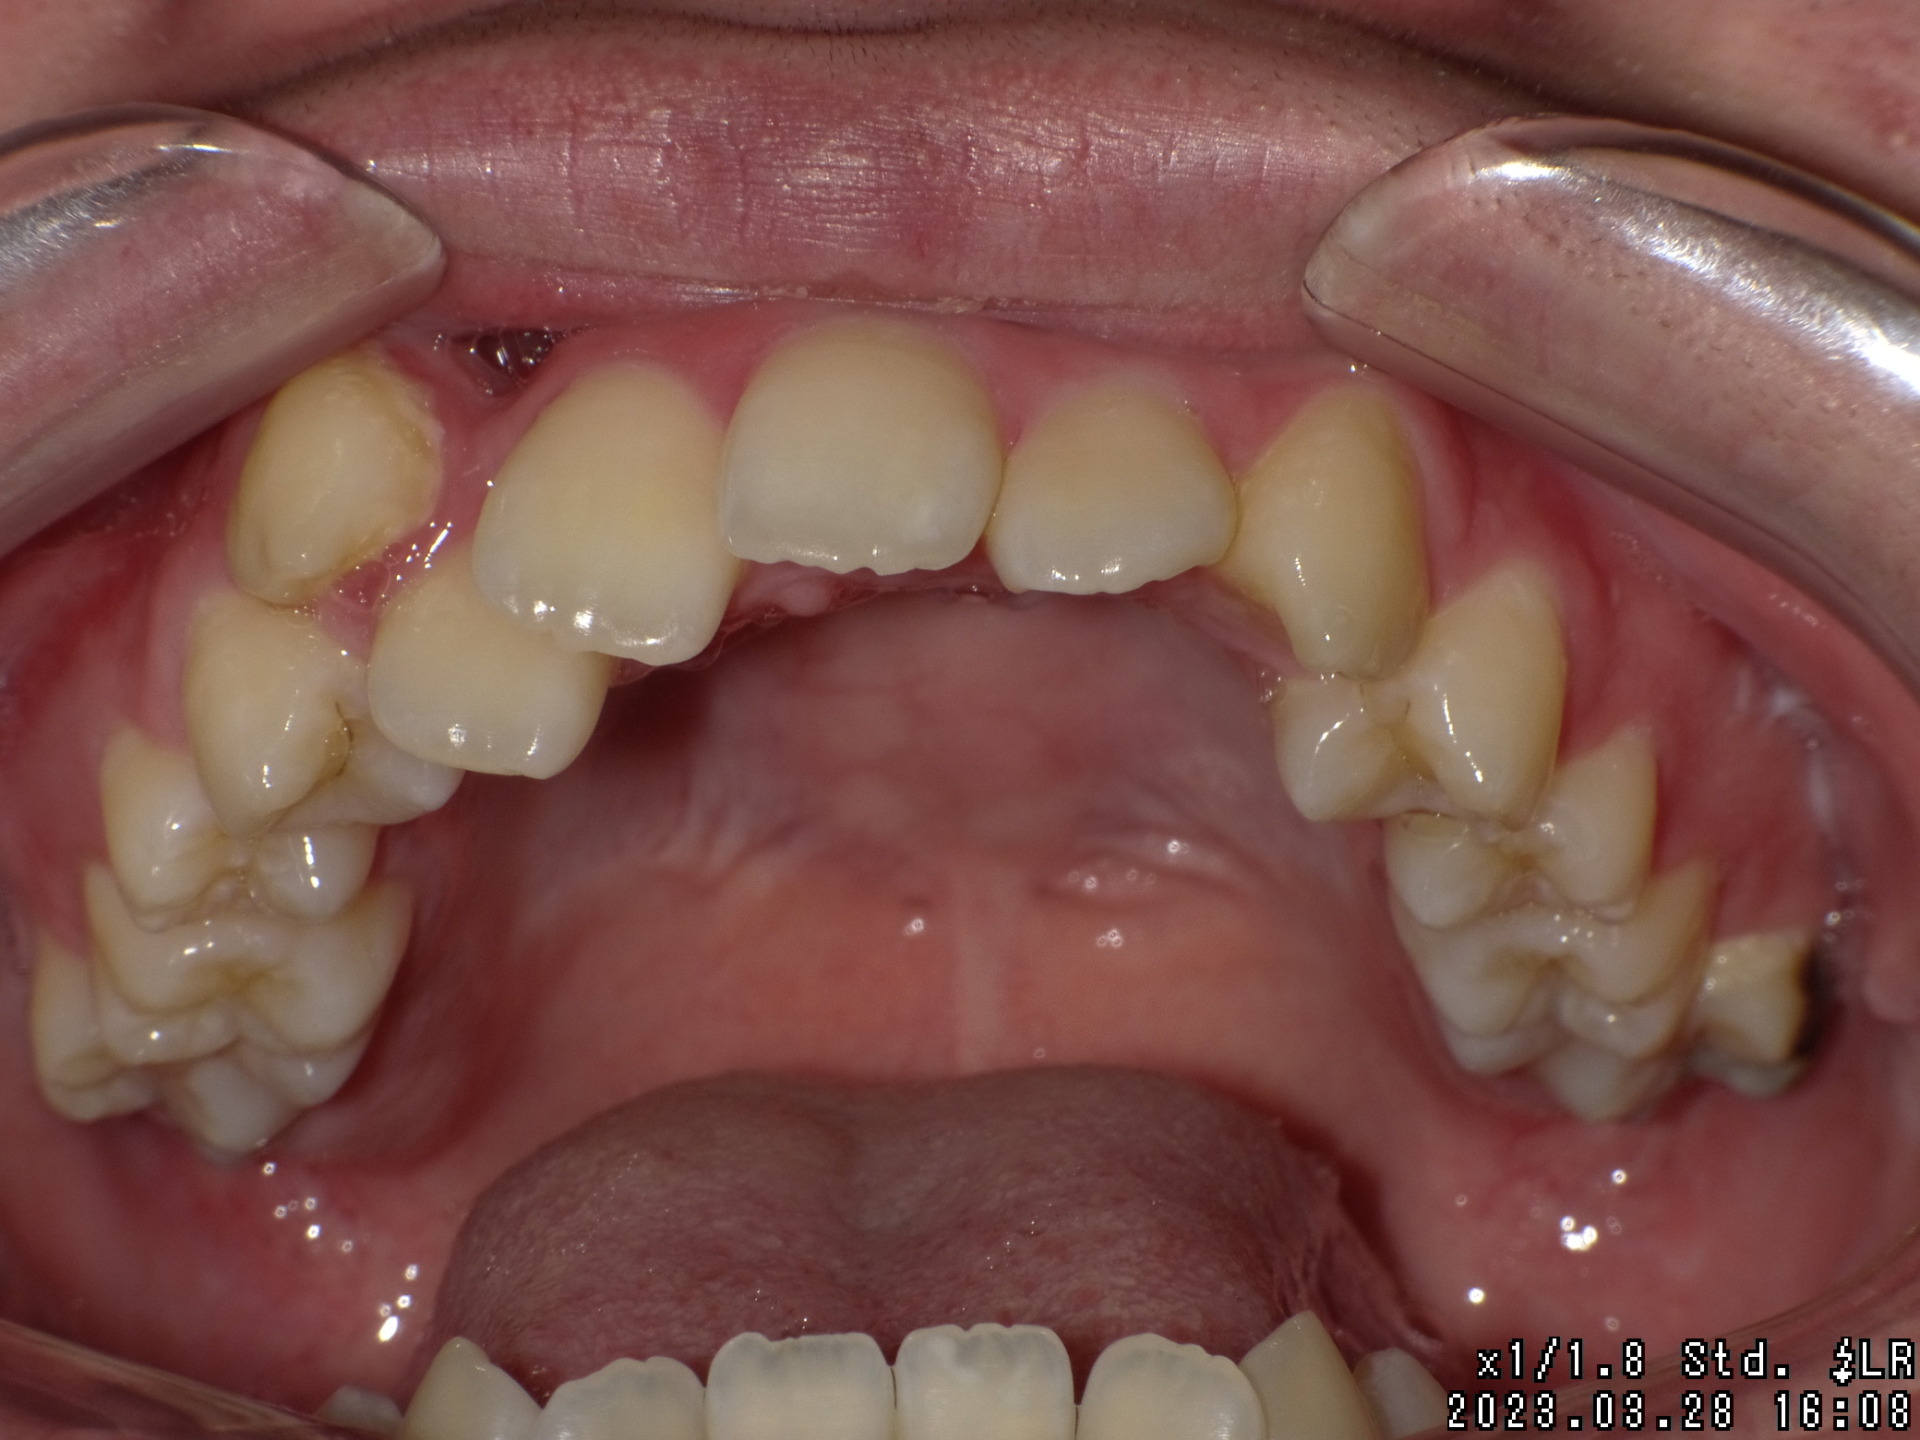

Before

| 症状 | 右上八重歯 上顎正中の著しいずれ |

| 通院目的 | 永久歯を抜かずに歯並びを治したい。 |

| 処置内容 | ディスタライザー・マルチブラケット装置 |

| デメリット・院長コメント | 永久歯を抜かない治療のデメリットは、治療期間が長いことです。 ただし、その後の人生の長さを考えると、健全な小臼歯を2本または4本抜歯の矯正治療よりも、はるかにメリットがあるといえます。 また、アーチが小さくならないので、舌が後ろに押し込まれないためいびき防止につながり睡眠の質の向上にもつながります。 |